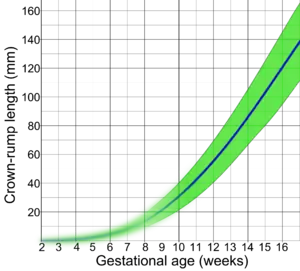

Crown-rump length (CRL) is the measurement of the length of human embryos and fetuses from the top of the head (crown) to the bottom of the buttocks (rump). It is typically determined from ultrasound imagery and can be used to estimate gestational age.

The embryo and fetus float in the amniotic fluid inside the uterus of the mother usually in a curved posture resembling the letter C. The measurement can actually vary slightly if the fetus is temporarily stretching (straightening) its body. The measurement needs to be in the natural state with an unstretched body which is actually C shaped. The measurement of CRL is useful in determining the gestational age (menstrual age starting from the first day of the last menstrual period) and thus the expected date of delivery (EDD). Different human fetuses grow at different rates and thus the gestational age is an approximation. Recent evidence has indicated that CRL growth (and thus the approximation of gestational age) may be influenced by maternal factors such as age, smoking, and folic acid intake. Early in pregnancy gestational age 8 weeks, it is accurate within about +/- 5 days but later in pregnancy due to different growth rates, the accuracy is less. In that situation, other parameters can be used in addition to CRL. The length of the umbilical cord is approximately equal to the CRL throughout pregnancy.

A commonly used estimate of gestational age in weeks is (as described by Verburg et al.[2]):

Gestational age estimation in days is carried out according to the equations:

; and SD of GA = 2.39102 + (0.0193474 × CRL).

Crown rump length before a gestational age of 9 weeks is extrapolated by assuming a crown rump length of 0 at a gestational age of 2 weeks, corresponding to an embryonic age of 0 weeks. This extrapolated part is blurred because of uncertain values. - 1 2 Verburg BO, Steegers EA, De Ridder M, Snijders RJ, Smith E, Hofman A, et al. (April 2008). "New charts for ultrasound dating of pregnancy and assessment of fetal growth: longitudinal data from a population-based cohort study". Ultrasound in Obstetrics & Gynecology. 31 (4): 388–96. doi:10.1002/uog.5225. PMID 18348183. S2CID 349860.